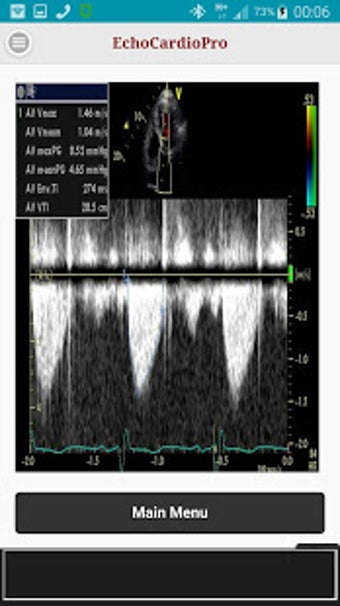

Aplikacja dostarcza kompleksowych informacji na temat echokardiografii przezklatkowej (TTE) i echokardiografii przełykowej (TEE) oraz ich odpowiednich korzyści w ocenie czynności skurczowej i rozkurczowej lewej i prawej komory, regionalnego ruchu ściany, wad zastawkowych serca i chorób osierdzia. Zawiera również szczegółowe informacje na temat różnych widoków, takich jak długoosiowy przysercowy, krótkoosiowy przysercowy, wierzchołkowy, podżebrowy, nadobojczykowy, śródprzełykowy, poprzezżołądkowy, głęboko poprzezżołądkowy i wysoko przełykowy.